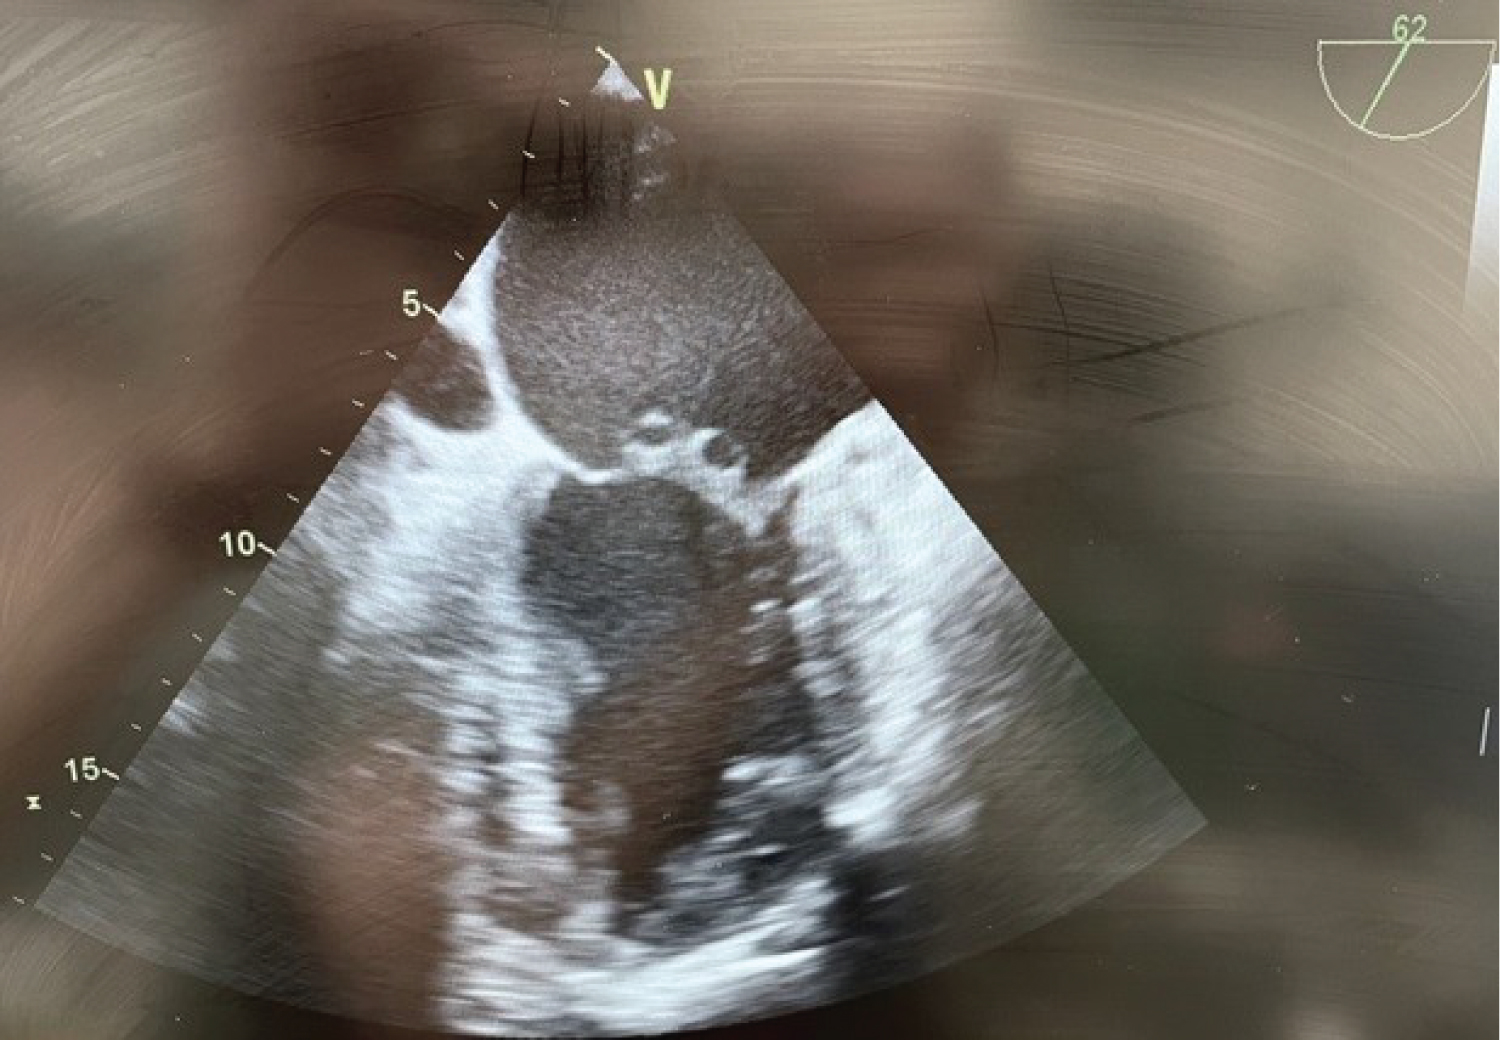

After an uneventful induction of anesthesia and placement of lines, a pre-bypass TEE confirms the presence of the A2 vegetation (Figure 1) and perforation with severe MR (Figure 2). The patient is also found to have moderate AI (Figure 3) and a patent foramen ovale (PFO) with left to right shunting (Figure 4). The surgeons are informed of the new findings and plans are made to close the PFO and to inspect the aortic valve. Aortotomy is made, and the aortic valve is found to have redundant tissue. Both the aortic and mitral valves are replaced with mechanical St. Jude's valves. The PFO is closed with a single suture, followed by de-airing of the heart under TEE guidance and weaning from CPB.

Figure 2: Pre-bypass TEE midesophageal mid commissural view illustrating MV vegitations. View Figure 2